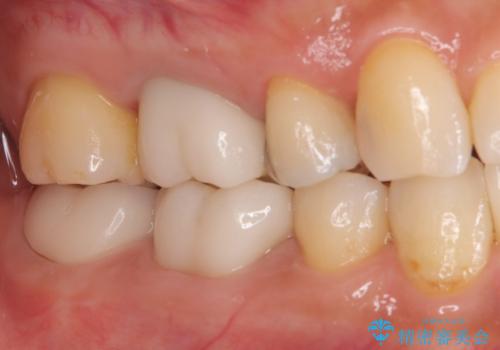

ズキズキ痛い歯 オールセラミッククラウンによる修復

- 冷たいもので長引く痛みがあることを主訴に来院されました。

抜髄を行い、オールセラミッククラウンにて修復を行いました。